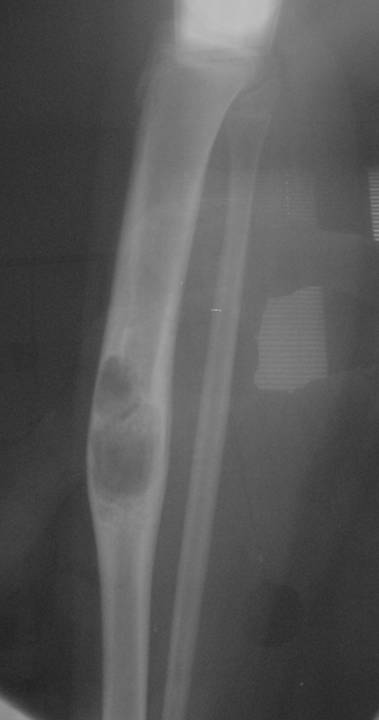

Sites:

- Predilection for tibia (90%)

- favoring diaphyseal portion of bone

Radiographic Presentation

- Sharply defined osteolytic defect (lobulated, multicystic, or “soap bubble”)

- May be considerable perilesional sclerosis